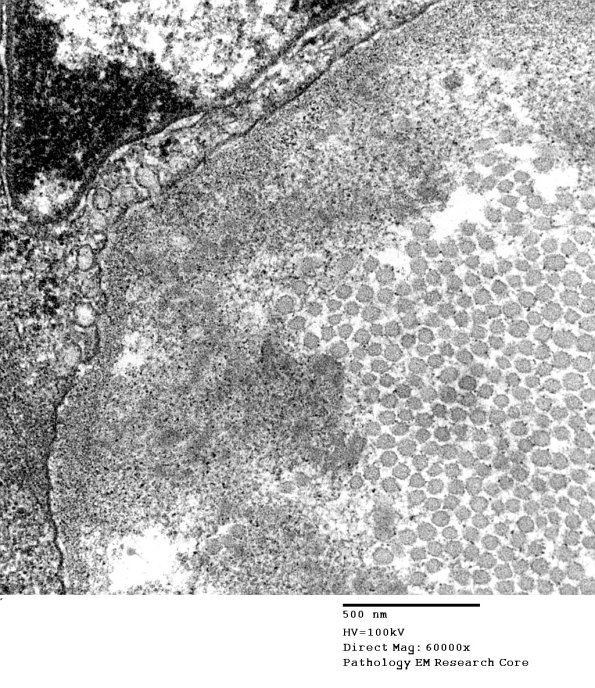

Higher magnification of image #1B11 showing both collagen and oxytalan. (electron micrograph)